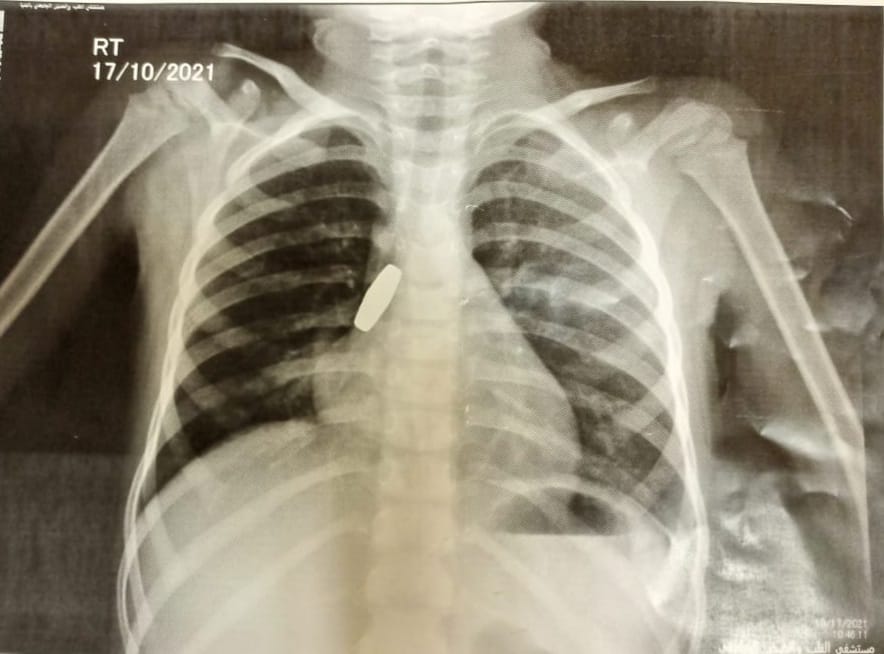

جدير بالذكر، أن الفريق الطبي بمستشفى ملوى التخصصي، جنوب المنيا، تمكن من استخراج جسم غريب من داخل الشعبة الهوائية اليمنى لطفلة، يشتبه كونها طلقة خرطوش.

و أعلن الدكتور محمد عبدالحكيم مدير مستشفي ملوي التخصصي جنوب المنيا، بنجاح الفريق الطبي لأول مرة من استخراج جسم غريب يشتبه في كونه «طلقة خرطوش» من بين الشعبة الهوائية اليمنى ابتلعتها طفلة تبلغ من العمر 4 سنوات.

وأضاف، على الفور تم تشكيل فريق طبي، وتم عمل أشعة عادية على الصدر بالإضافة إلى عمل أشعة مقطعية على الصدر أيضا وبعد التأكد من مكان وجود الجسم الغريب، تم عمل منظار شعب هوائية لاستخراج الجسم الغريب.